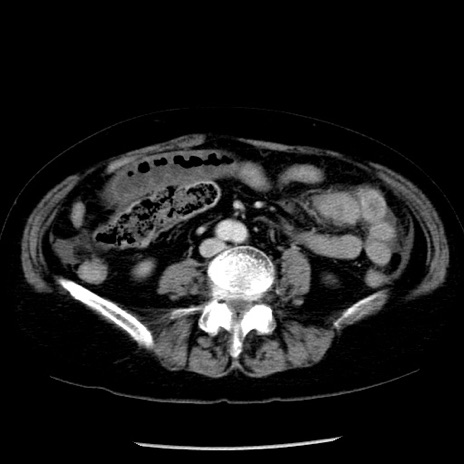

症例13(横断像)

【症例】70歳代女性

【主訴】腹痛、嘔吐

【現病歴】15時間程前(昨晩)より腹痛あり。今朝になっても症状の改善なく、嘔吐あり。腹痛も増悪あり、救急外来受診。

【既往歴】子宮癌全摘術後

【身体所見】意識清明、BP 121/72mmHg、P 74bpm、SpO2 100%(RA)、腹部:平坦・軟、腸雑音ほぼ聴取せず。下腹部・心窩部・臍左上に圧痛あり。反跳痛なし。

【データ】WBC 10600、CRP 0.15